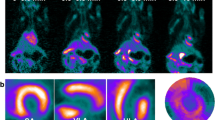

Following MI, there is an upregulation of [18F]LW223 binding within the heart, although in absence of perfusion correction this results in a lower SUV within the infarct (LV anterior wall, Fig. 1a–b). The kinetics of [18F]LW223 in the healthy and infarcted heart display a Morrison’s kinetics binding profile, whereas in the brain the kinetics can be described by the Michaelis–Menten binding principles (Fig. 1b–c) [13].

[18F]LW223 distribution and kinetics in naive rats and rats with myocardial infarction (MI). a Example sagittal SUV images, which are non-perfusion corrected, top row shows the heart and the bottom row the brain. The cardiac areas typically included in the CT drawn global heart VOI are indicated by the broken white line, and the myocardium subsampled within the anterior wall is indicated by a single asterisk (*). A, anterior; P, posterior; H, head and F, foot. b SUV time activity curves for VOIs in the heart and c) brain. Mean ± SEM, n = 6 for naive and n = 9 for MI